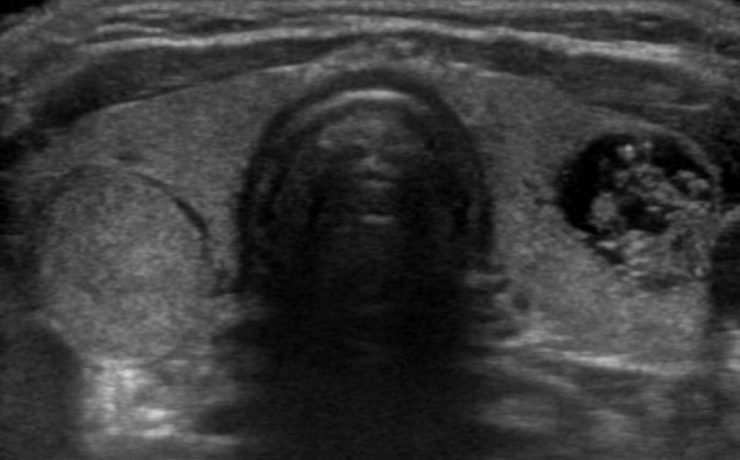

La ecografía del bazo.

La ecografía del bazo La ecografía del bazo es una parte fundamental del examen ecográfico completo, en el cual se evalúa el tamaño, forma, ubicación y parénquima del bazo, siendo necesario examinar y documentar estos aspectos detalladamente. Una de las principales ventajas de la ecografía es su amplia disponibilidad, bajo